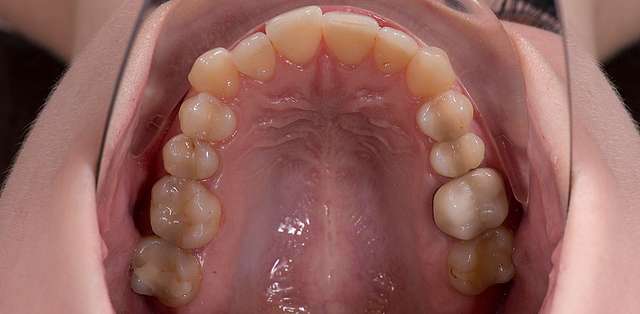

One of the advantages of lingual braces, outside of the obvious one (the fact that it's socially invisible) is that it will preserve intact the buccal surface of teeth. It has a somewhat more complex and difficult biomechanic to manage, but it has its niche for patients who want their teeth straightened but don't want braces to be visible. Lingual braces are usually made from gold, have a high degree of biocompatibility and prevent secondary caries.

Here we had to deal with a significantly deviated midline, needed to bring one canine on the arch and basically realign teeth on both arches. To finish we did some composite details. When existing teeth have naturally beautiful shapes, orthodontics is many times a superior alternative to prosthetic treatment. It has one disadvantage: requires more time.